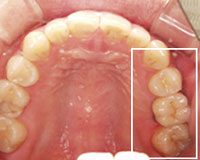

治療後

左上奥から2番目がインプラントを埋入しセラミックを入れた歯です。

十分な隙間を作ってからインプラントを行なったので、歯を削ることなく治療することができました。.